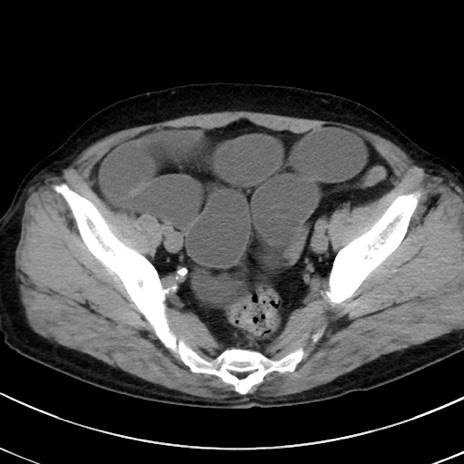

症例38(横断像)

【症例】70歳代 男性

【主訴】腹痛・嘔吐

【現病歴】昨晩より、嘔吐・腹痛あり。今朝になっても嘔吐あり。来院。

【既往歴】心臓バイパス手術、開腹胆摘、腸閉塞

【身体所見】BP 107/71mmHg、HR 116/min、腹部:平坦、軟、下腹部に軽度圧痛あり。反跳痛なし。

【データ】WBC 15100、CRP 0.32